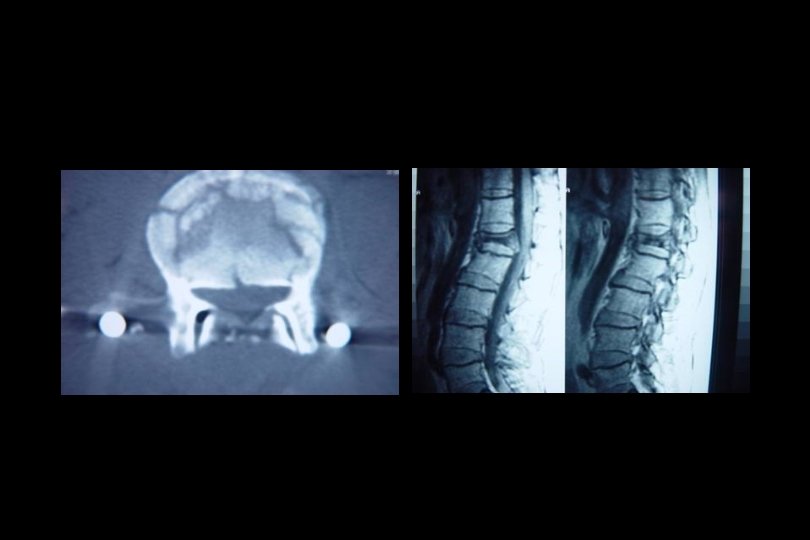

Direkt grafi • • Omurga kanalı ön-arka çapını (13 mm. ) Omurların kontur ve düzlemlerini Kanal içindeki kemik parçacıklarını Lamina, pedikül veya nöral arkların basit veya ortak kırıklarını • Yumuşak doku mesafesinde artmayı – erişkin; C 1=10 mm, C 2 -4=5 -7 mm, C 5 -7=22 mm. – Çocuk; C 1 -4= değişir, C 5 -7=14 mm.

Direkt grafi • • • Torakal ve/veya lomber yaralanmada Pediküllerin iki yanlı simetrisi Omurlarası disk mesafesinin yüksekliği Spinoz çıkıntılarının orta hatta olup olmadığı Omurların konturları Omurga düzlemi